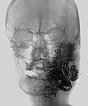

Complete filling of the entire nidus of the AVM using ethylene-vinyl alcohol copolymer (EVOH). This is visible in the radiograph shown here (AP) as a black, reticular radiopaque cast specimen within the occluded AVM vessels.

Filling of the entire nidus of the AVM using ethylene-vinyl alcohol copolymer, which is visible in the radiograph shown here (lateral view) as a black, reticular radiopaque cast within the occluded AVM vessels.